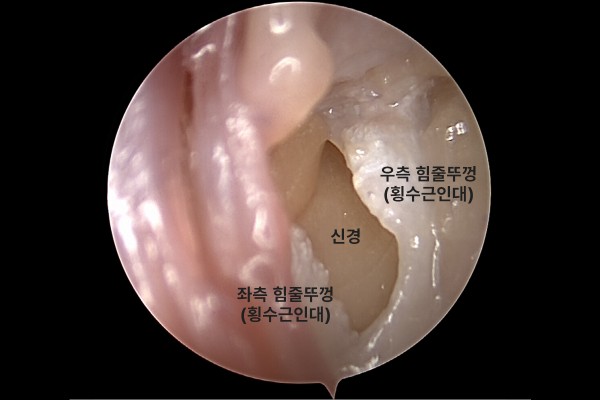

내시경 유리술은 내시경을 이용하여 손목 내부를 실시간으로 확인하면서 수술을 진행하기 때문에, 주변조직 손상 없이 힘줄을 압박하는 힘줄뚜껑(횡수근인대)만을 선택적으로 절개하여 정중신경에 가해지는 압박을 해소합니다. 또한 횡수근 인대를 절개할 때 정밀한 수술에 사용하는 하키나이프를 사용하기 때문에 더욱 세밀한 수술이 가능합니다.

내시경 사진을 보시면, 수술기구 진입을 위한 입구를 확보하고,